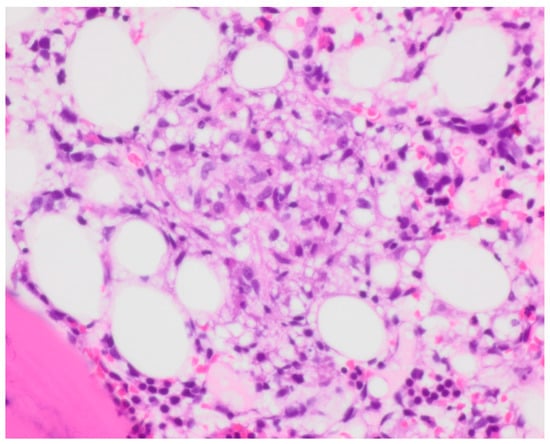

Bone marrow biopsy showed slightly hypercellular marrow with increased macrophages (Figure 1) present as diffuse infiltrates, loose aggregates (Figure 2), and tighter granulomatous aggregates. Acid-fast bacilli and fungi were negative. Occasional macrophages demonstrated the involvement of nucleated red cells and myeloid cells on the aspirate smear (Figure 3), compatible with hemophagocytosis.

Figure 1. Clot section, macrophages. Hemotoxylin and Eosin (H and E) staining with 40× objective magnification.